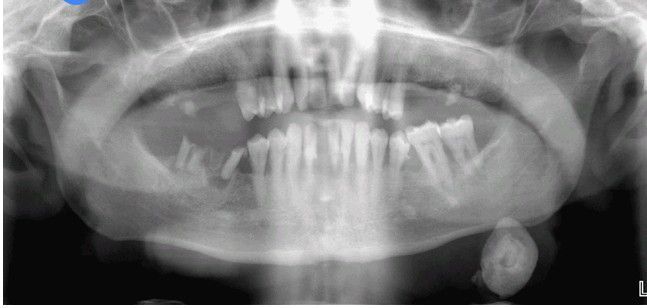

Sialolithiasis

. Radiopaque mass located at the left angle of the mandible.

Mandible

Angle